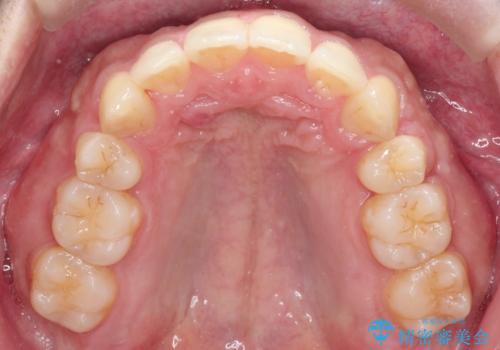

【審美ワイヤー】奥歯のガタガタを治したい

- 歯並びの凸凹を主訴に来院されました。

スペースが必要なため、抜歯を行なって治療を行いました。

奥歯の捻れが強く治療期間がかかりましたが、綺麗な仕上がりに満足していただきました。